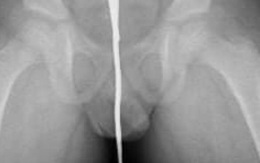

Bệnh viện sơ tán khi cấp cứu bệnh nhân bị kẹt đạn pháo trong hậu môn

Các bác sĩ tại một bệnh viện ở Pháp đã rất bàng hoàng khi một bệnh nhân lớn tuổi đến cấp cứu với một quả đạn pháo kẹt trong hậu môn.